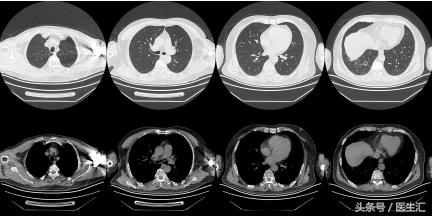

治疗后复查胸部CT(2011.11.18)